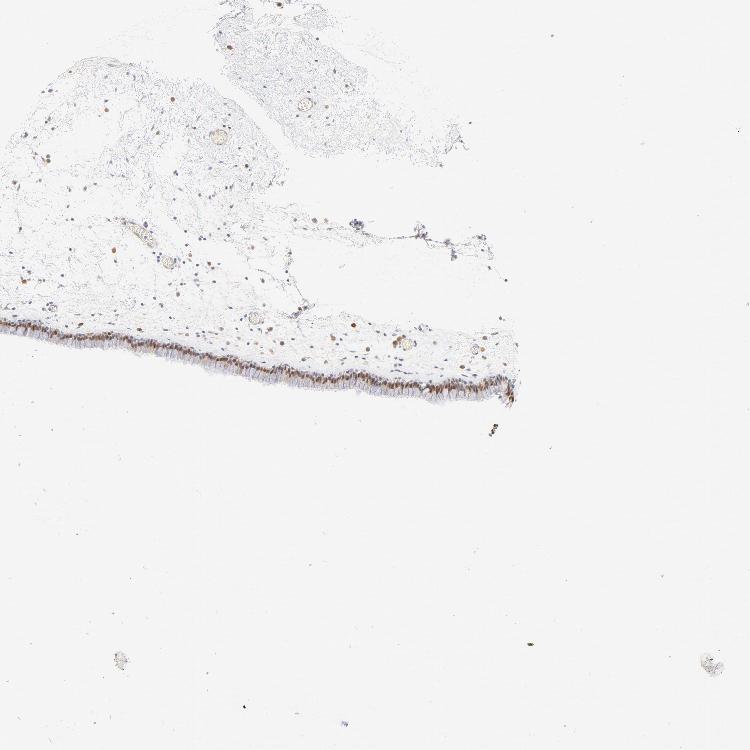

TISSUE PRIMARY DATA NASOPHARYNX Show tissue menu

Nasopharynx

NASOPHARYNX - Antibody stainingi

Antibody staining in the annotated cell types in the current human tissue is reported as not detected, low, medium, or high, based on conventional immunohistochemistry profiling in selected tissues. This score is based on the combination of the staining intensity and fraction of stained cells.

Each image is clickable and will lead to virtual microscopy that enables deeper exploration of all samples and also displays staining intensity scores, fraction scores and subcellular localization as well as patient and tissue information for each sample.

Antibody HPA003316Antibody HPA003479

Basal cells -Not detected

Ciliated cells (cell body) -High

Ciliated cells (cilia axoneme) -Not detected

Ciliated cells (ciliary rootlets) -Not detected

Ciliated cells (tip of cilia) -Not detected

Respiratory epithelial cells Medium-